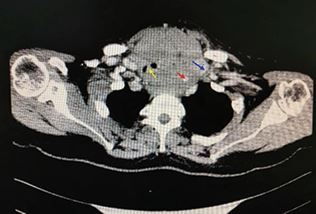

Intervention: Under general anesthesia, a V-V ECMO assisted thyroid biopsy and tracheostomy were performed. Intraoperative resection of anterior thyroid tissue for pathological diagnosis, with subsequent tracheal exposure and tracheostomy. Pathological examination confirmed diffuse large B-cell lymphoma (germinal center origin, Ann Arbor stage IV XB). Postoperatively, the patient was transferred to hematology for further treatment. Follow-up CT at two months showed significant tumor regression and a stable tracheostomy (Figure 2). Electronic laryngoscopy showed no obvious tracheal stenosis (Figure 3).Follow-up is ongoing

Figure 2 Neck CT demonstrates significant post-treatment reduction in the left thyroid lobe mass, which no longer causes significant compression or obstruction of the cervical trachea. A tracheostomy has been performed.